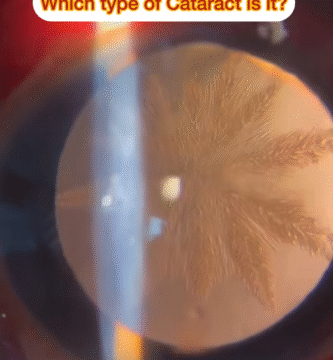

June is Cataract Awareness Month – Protect Your Sight Through Early Detection